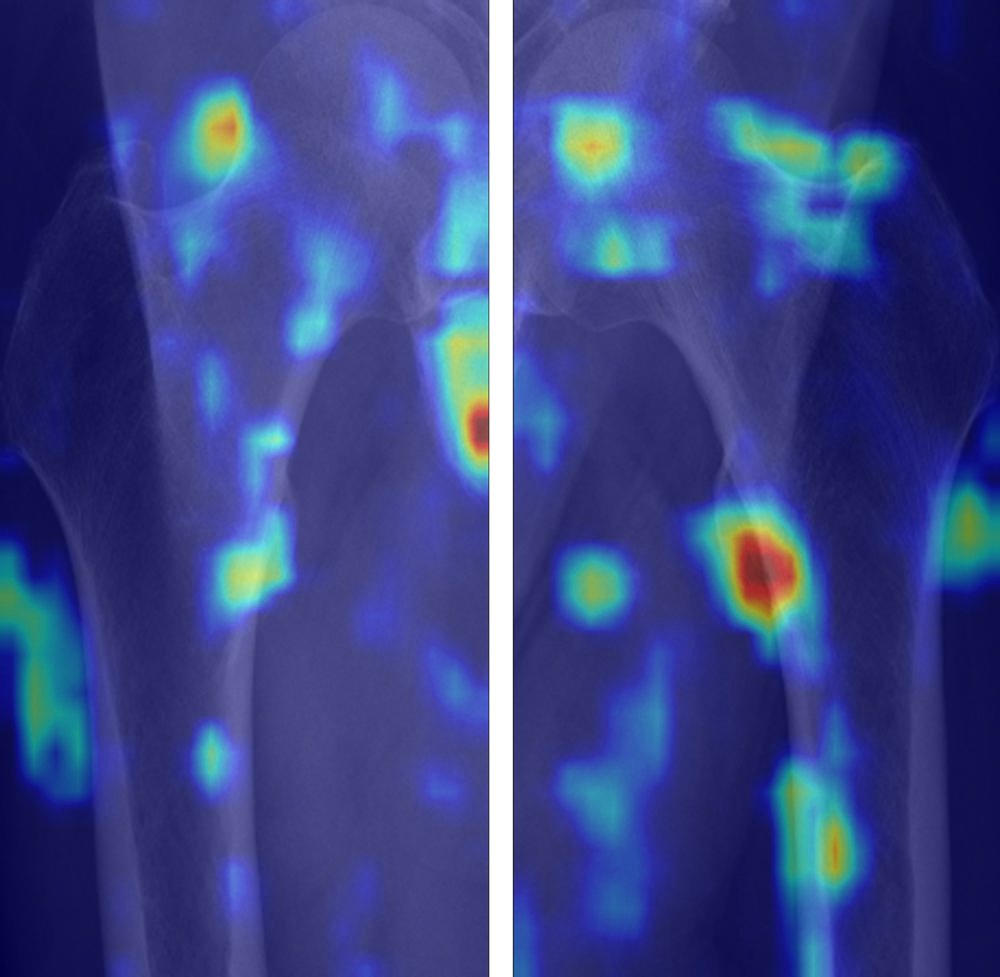

Figure 8. Gradient-weighted class activation mapping (Grad-CAM) images of false-positive cases for diagnosis of osteoporosis. False-positive cases highlighted the medial cortex and lateral surrounding soft tissue area, which reflect the cortical thinning and incremental role of surrounding soft tissue for predicting osteoporosis. We used the jet colormap scale, where the red color stands for high relevance, yellow for medium relevance, and blue for low relevance.

High-res (TIF) version